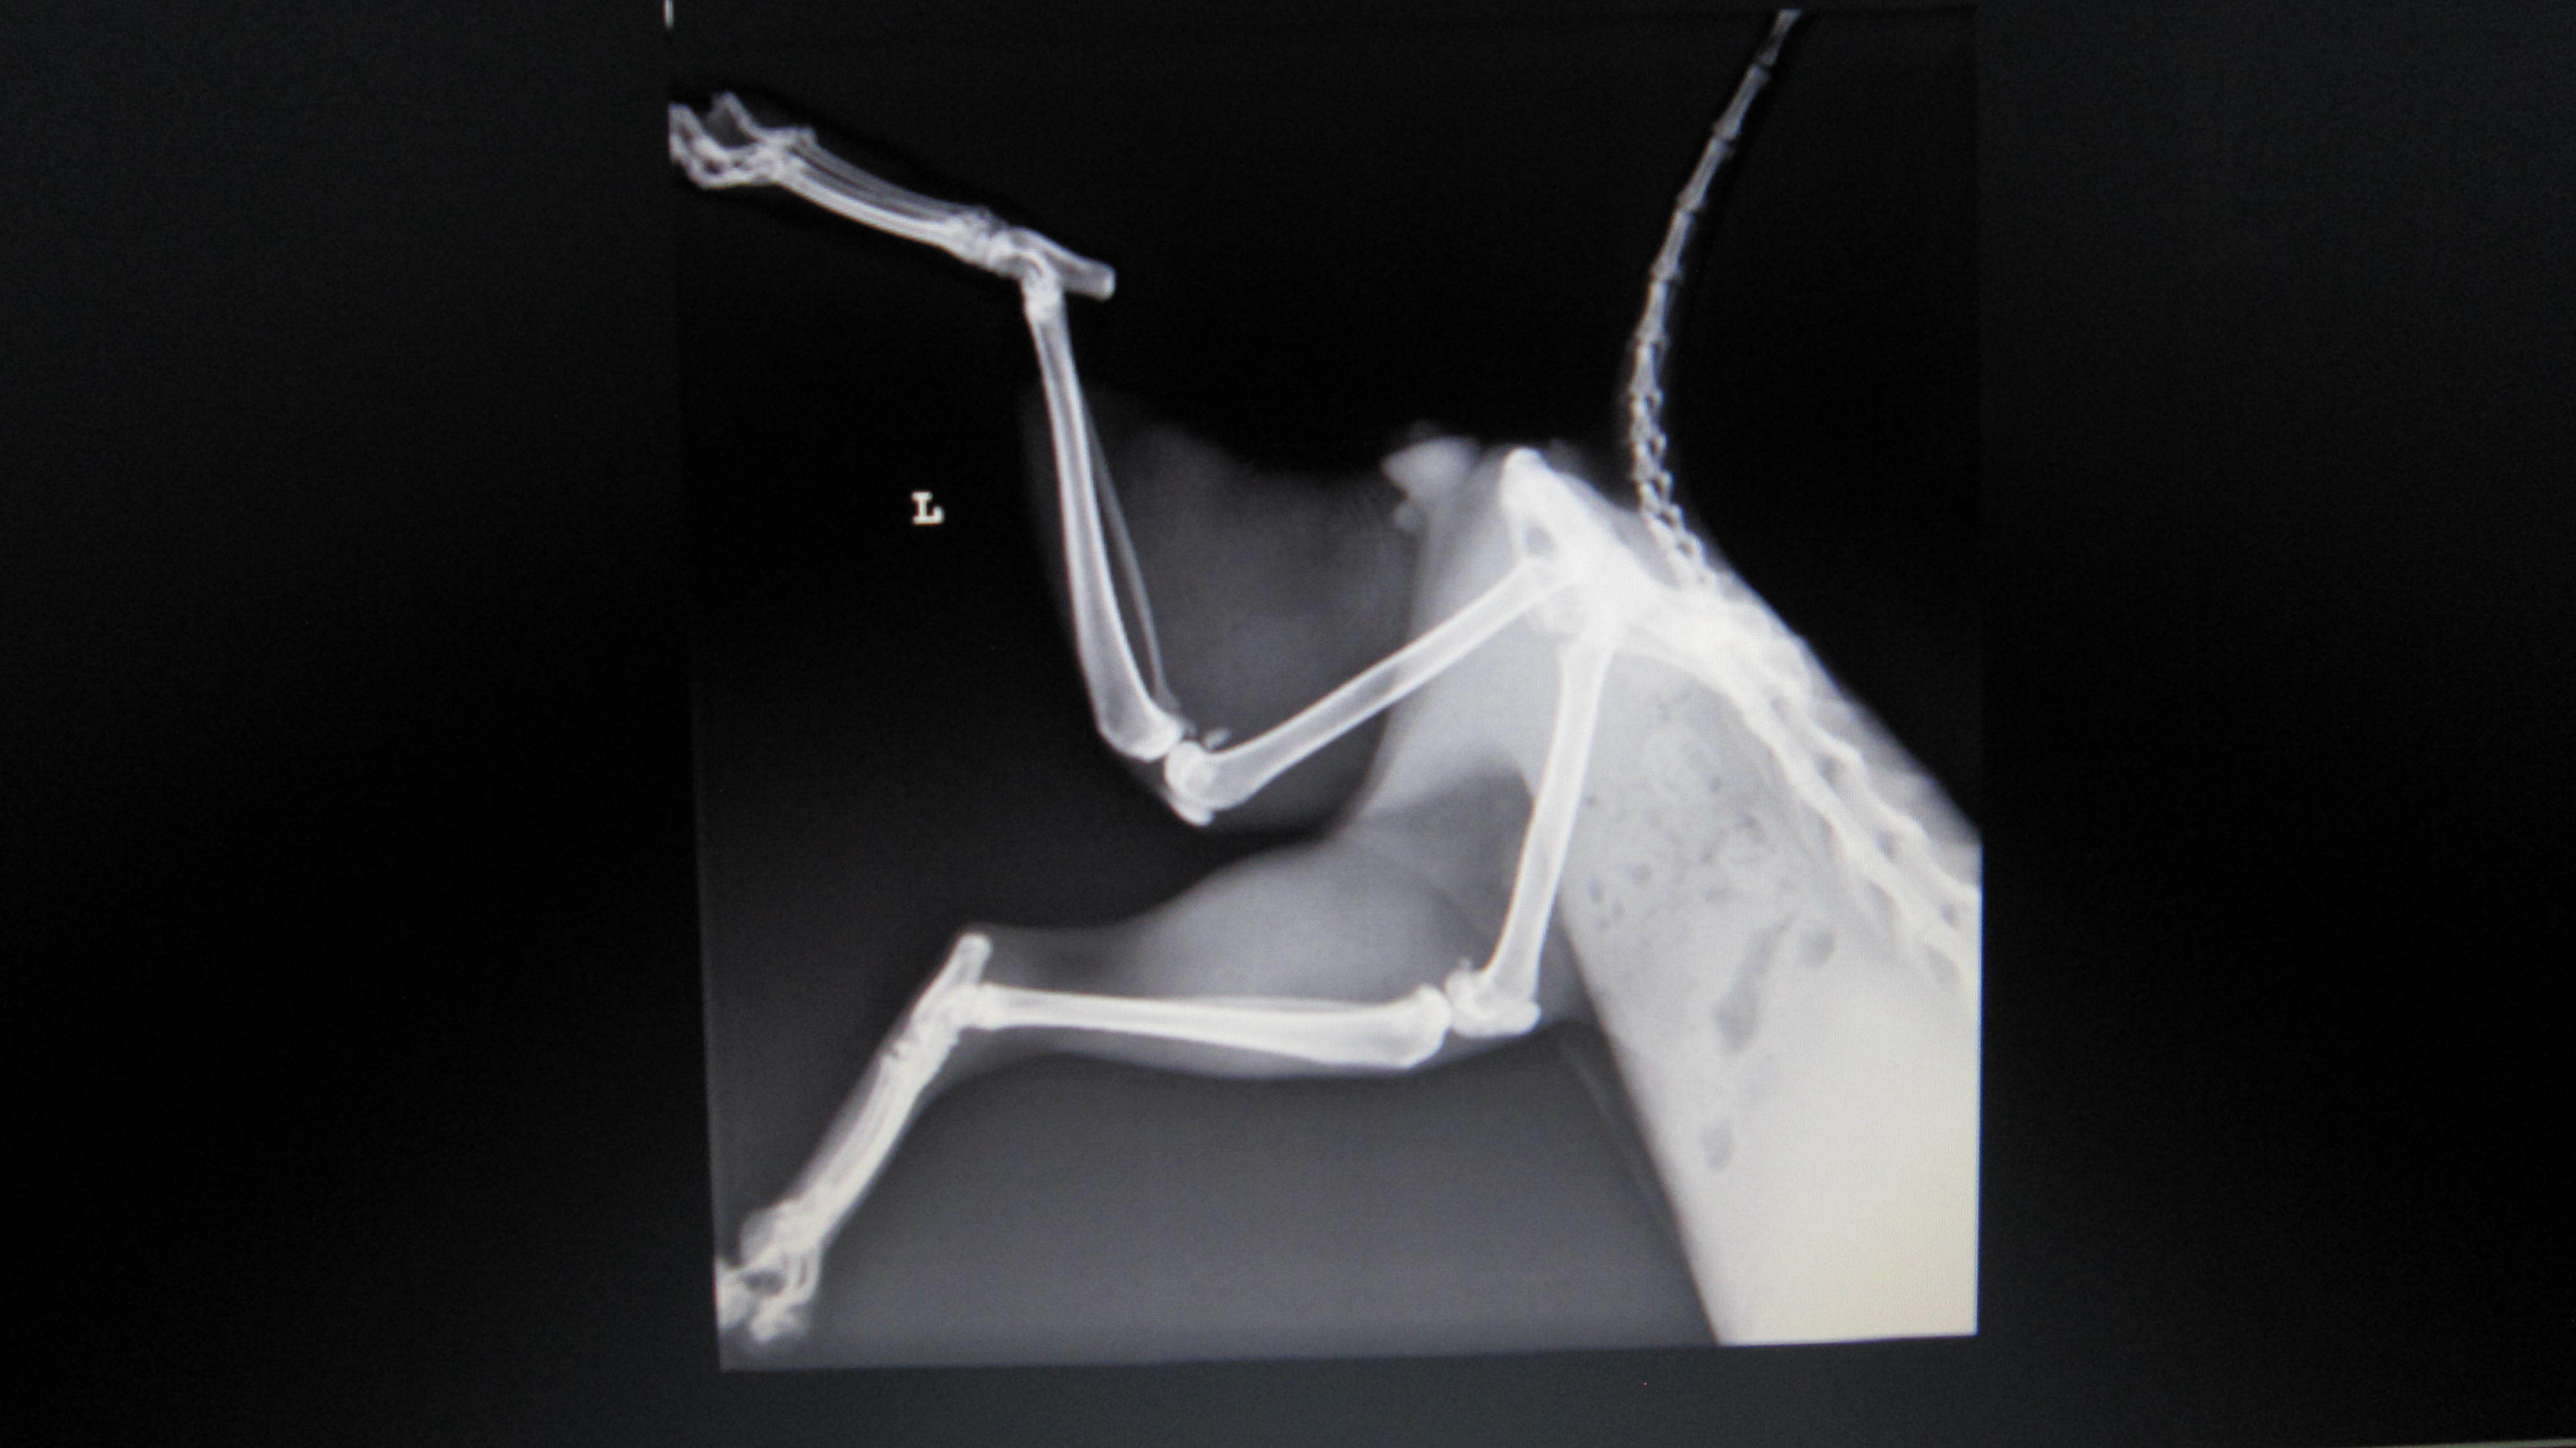

主題: 八德市大湳市場倒在路旁的斷腿貓 (第二次醫助通報) 申請者姓名: 李明明 花色: 申請日期: 2013-06-09 22:30:55 申請者部落格: 申請者臉書網址: 所在縣市/合作醫院: 台北市/長青動物醫院 治療費用: 27160元 需求人數: 29人 已結案 (2013-08-06 14:00:31) 報名人員: 白婷(已付款)、Forest(已付款)、Alison Lee(已付款)、euca(已付款)、言則(已付款)、miraai(已付款)、周小蕾(已付款)、sfeng(已付款)、vivian(已付款)、Rachel Chen x2(已付款)、宋小璉 x2(已付款)、chiawei(已付款)、suxiwen(已付款)、Ping Hussard(已付款)、PS Yeh x2(已付款)、Vinnie Hsu(已付款)、Iris Hsu、Iris Hsu(已付款)、nicole chen(已付款)、Sunny Chen、Sunny Chen(已付款)、蘇小優(已付款)、林嘉南(已付款)、Nonie Huang(已付款)、Ariel Yu-Ting Tu、Kyra Chu(已付款)、林艾蓁(已付款)、chiawei(已付款)、JASON(已付款)、 候補人員: 動物病情說明: 5/11白蛋白已由1.9上升至2.3,食慾佳;每天仍須早晚兩次左後腳背傷口清創,並配合抗生素治療,促進傷口癒合,醫院將視傷口癒合情形調整清創次數。腹水部分先以補充營養與熱量,觀察白蛋白指數回升情形,決定後續治療。另,醫生告知,觀察馬太昨天 (5/12) 有癲癇發作一次,目前繼續觀察中。左前肢雖骨折但已能稍微站立,恢復情形較佳;後肢因關節韌帶受損、腳背傷口清創&肌肉腫脹,恢復較緩慢。 動物近況說明: 斷腿貓(馬太) 6/2 出院,醫療費用合計27,160元 , 已帶回桃園就近照顧,限制活動並定時每日傷口換藥,穩定復原中。